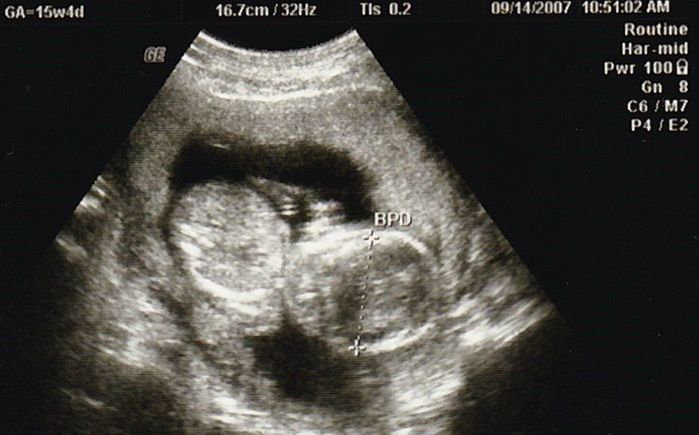

妊娠15週目のエコー写真

やっと安定期に入りました。「性別は、次回の検診のときに聞きたければ教えますよ」と言われていて、今回“男の子”と教えてもらいました。手で目をこすっているような様子など、かわいいな、早く会いたいな、名前どうしようかな、と思いを巡らせていました。退職したため、夫の休みに出産前最後の旅行もしました。